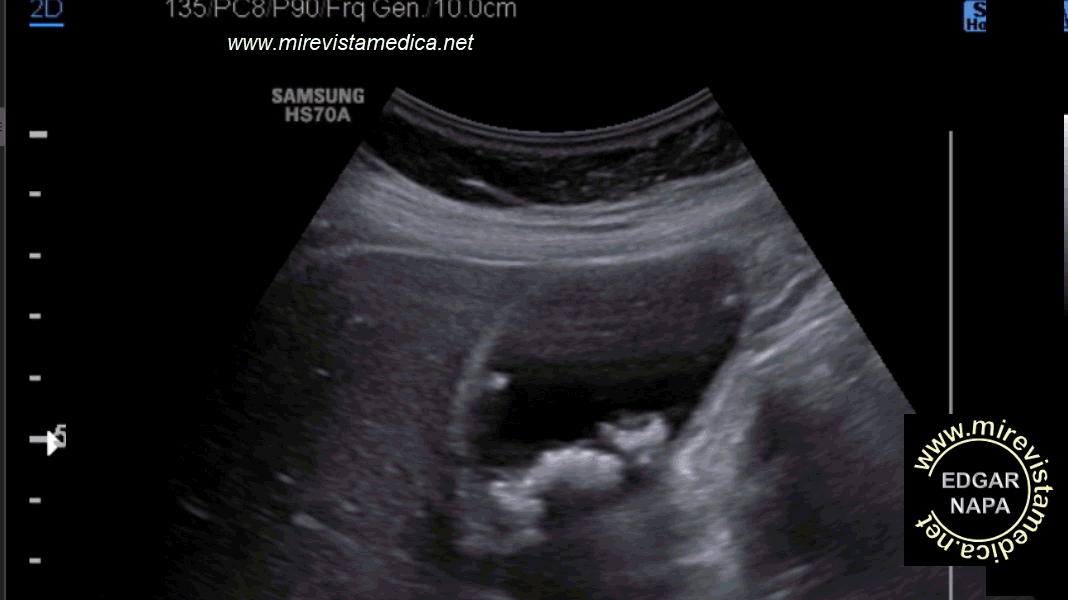

Hallazgos tomográficos en la colecistitis aguda calculosa.

- Distensión de la vesícula biliar, que es > 5 cm en el eje corto.

- Engrosamiento de pared vesicular, > 3 mm, con realce al contraste de su pared con imágenes de "hebras de grasas" de localización pericolecística.

- Calculo calcificado (15% de los casos).

- Realce al contraste del parénquima hepático adyacente.